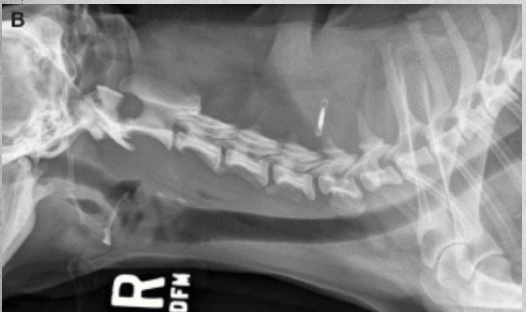

how to fix Atlantoaxial instability?

Angular relationship between the lamina of C1 and C2 in left image and fixed in right image.